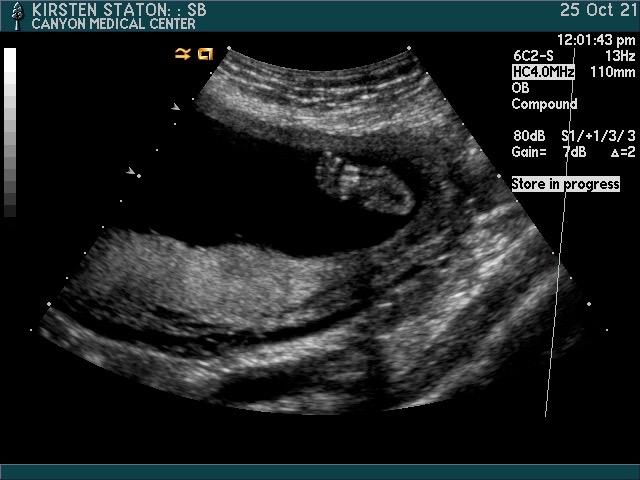

Tyler came home from London HALLELUJAH LORD ALMIGHTY! I was anticipating him being at home so he could help me wrangle, but most of all so I could feel less isolated in this weird in-between of unknown. I dropped Si off with a friend, picked up T from work, and we drove the wet, cold, dark, depressing drive to the doctor. The technician did a comprehensive scan of his heart. After she was done, we were asked to go to another room to chat with the doc. My heart sank. This. Was bad. We looked at one another; we knew it. We sat in the room, and the doctor proceeded to tell us that our baby had transposition of the great arteries-TGA. TGA is one of the rarest and most fatal congenital heart defects. There is no cure; the chance of stillbirth is high–if you make it full term, open-heart surgery will be done the first week of life. This surgery is a milestone if he does make it. There is a higher chance of other genetic disorders, a higher chance of abnormalities, and lastly, not sure if this will be one of many surgeries, etc. etc. etc. blah. blah. blah. She reminded us we had two weeks to terminate and I completely tuned everything out from there. I became more concerned I would throw up on the table than listen to anything else this woman had to say. I wanted to punch this innocent doctor in the only spot visible on her face, right in the place between her protective goggles and covid mask. We made an appointment for the next day with the cardiologist and the elevator shut. I began to wale. The waling did not stop.